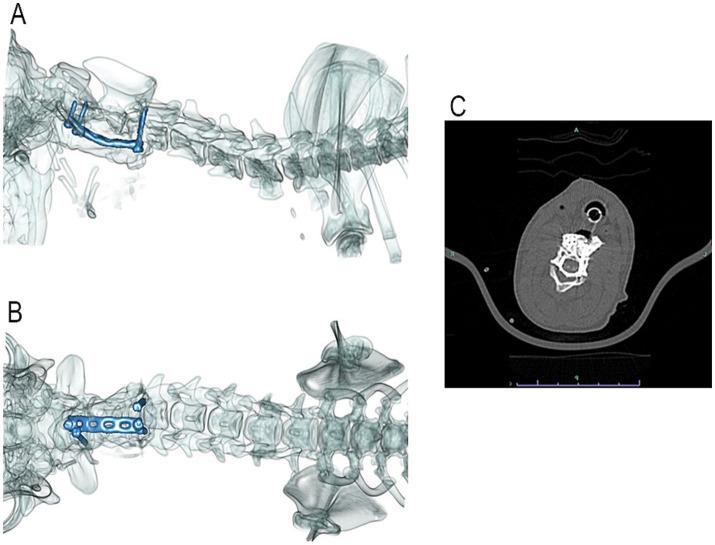

Veterinary cuttable plates (VCPs) were used to maintain reduction and provide reinforcement in screw and polymethylmethacrylate (PMMA) repairs of C2 vertebral fractures in two dogs. A 6-month-old male intact 3.8 kg Shih Tzu and a 4-year-old male intact 30.5 kg Golden Retriever presented after motor vehicle accidents. Computed tomography (CT) scans revealed fractures of the C2 vertebrae in both dogs. Fractures were reduced and stabilized with a combination of cortical screws, VCPs, and PMMA. The novel technique utilized veterinary cuttable plates positioned between screws cranial and caudal to the fracture for distraction and reduction of the fractures and can be incorporated into the acrylic. Post-operative imaging showed adequate fracture reduction and relief of spinal cord compression. Recheck examinations demonstrated a return to normal and near-normal neurologic function in both patients.

在两只犬的C2椎体骨折的螺钉和聚甲基丙烯酸甲酯(PMMA)修复中,使用兽医可切割钢板(VCP)来维持复位并提供加固。一只6个月大、体重3.8千克的未绝育雄性西施犬和一只4岁、体重30.5千克的未绝育雄性金毛寻回犬在机动车事故后就诊。计算机断层扫描(CT)显示两只犬均有C2椎体骨折。通过皮质螺钉、VCP和PMMA的联合使用,骨折得以复位并稳定。这项新技术利用置于骨折部位头侧和尾侧螺钉之间的兽医可切割钢板来牵引和复位骨折,并且可以与丙烯酸材料结合使用。术后影像学检查显示骨折复位良好,脊髓压迫得到缓解。复查显示两名患者的神经功能均恢复到正常或接近正常。